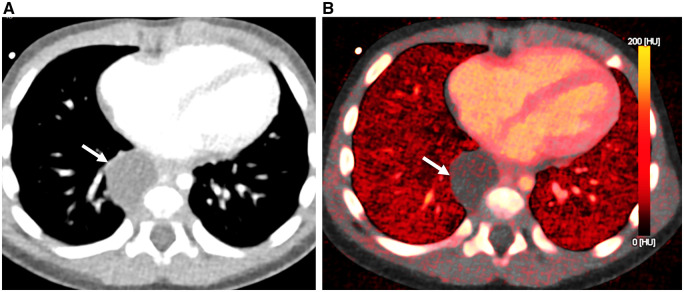

Photon-counting detector computed tomography (PCD-CT) is the most recent advancement in CT technology and has the potential to change clinical practice. Unlike conventional energy-integrated-detector (EID) that uses a two-step process to convert X-rays into a digital signal, PCD-CT directly converts photon energies into electronic signal. The advantages of PCD-CT over EID-CT are higher spatial resolution, electronic noise reduction, higher contrast-to-noise ratio, improved radiation dose efficiency, and intrinsic spectral imaging. Successful implementation into clinical practice requires adaptations in CT protocols. In this review, we summarize the basic principles of PCD-CT and technical scanning factors followed by a discussion of its clinical benefits in pediatric pulmonary and cardiovascular imaging.